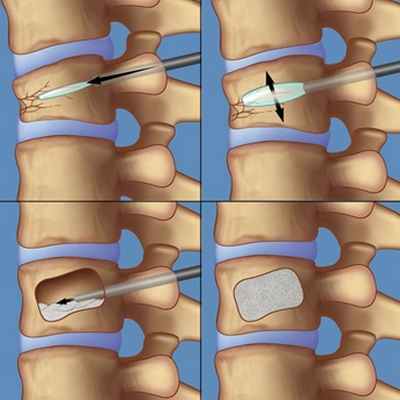

Вертебропластика

Эта процедура наиболее полезна для уменьшения боли. Она также укрепляет поврежденную кость, позволяя пациентам восстанавливаться быстрее. С помощью иглы, под контролем рентгена, в область трещины позвонка вводится цементирующее вещество, полиметилметакрилат (ПММА). Цемент затвердевает в течение 15 минут. Это фиксирует кость и предотвращает дальнейшее разрушение и снижает болевые проявления у более 80% пациентов.

Кифопластика

Кифопластика - еще один хирургический метод лечения компрессионных переломов позвонков. Как и при вертебропластике, эта процедура уменьшает сильную боль и укрепляет треснутую кость. Кроме того методика позволяет избежать развития кифоза в будущем .